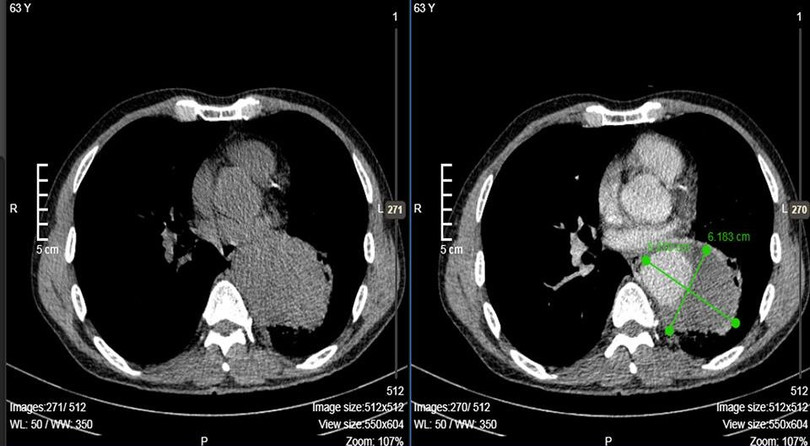

| Ảnh chụp CT cho thấy động mạch của anh Q. bị phình |

| Động mạch chủ là động mạch lớn nhất trong cơ thể đưa máu từ tim đi nuôi toàn bộ cơ thể. Vị trí của động mạch chủ nằm ở ngực, phía trước cột sống, cấp máu cho tim, não và đầu cổ, cột sống. Kích thước bình thường của động mạch chủ ngực tăng dần cùng với tuổi bệnh nhân và nằm trong khoảng từ 2 đến 3,5 cm. Phình động mạch chủ là hiện tượng tăng kích thước động mạch chủ dạng hình túi hoặc hình thoi, gây ra do một điểm yếu trên thành mạch. Đường kính động mạch chủ ngực càng lớn, nguy cơ gây vỡ phình càng tăng dẫn đến nguy cơ tử vong càng cao. |